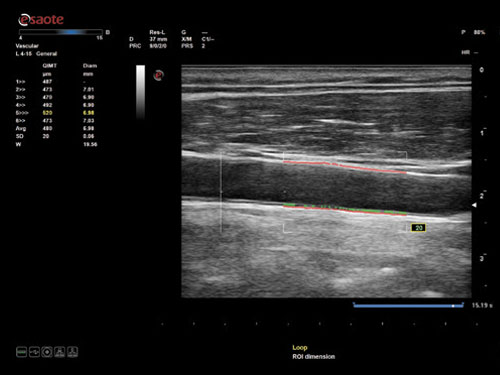

QIMT: Automatická detekce tloušťky média Intima v reálném čase, včetně směrodatné odchylky a indexu spolehlivosti, na základě analýzy RF signálu.